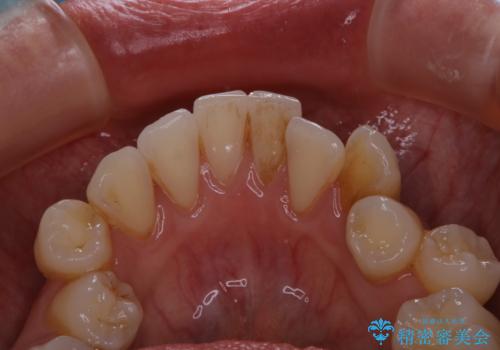

久々の来院で歯のクリーニング PMTC60分コース

- しばらく来院できなかったため、全体的にチェックとクリーニング希望でした。PMTC60分コースを行いました。

歯にステイン(着色)や歯石などが付着していると、汚れなのか虫歯なのかの判別が分かりにくく、正確な診断ができないことがあります。

そのため、定期的に専門的な機械や材料を使用したクリーニング(PMTC)をすることで、ご自身本来の歯の状態となります。より、健康なお口の維持をするためには、痛みや症状などが無くてもPMTCを行いお口の中の環境を綺麗にすることがおすすめです。